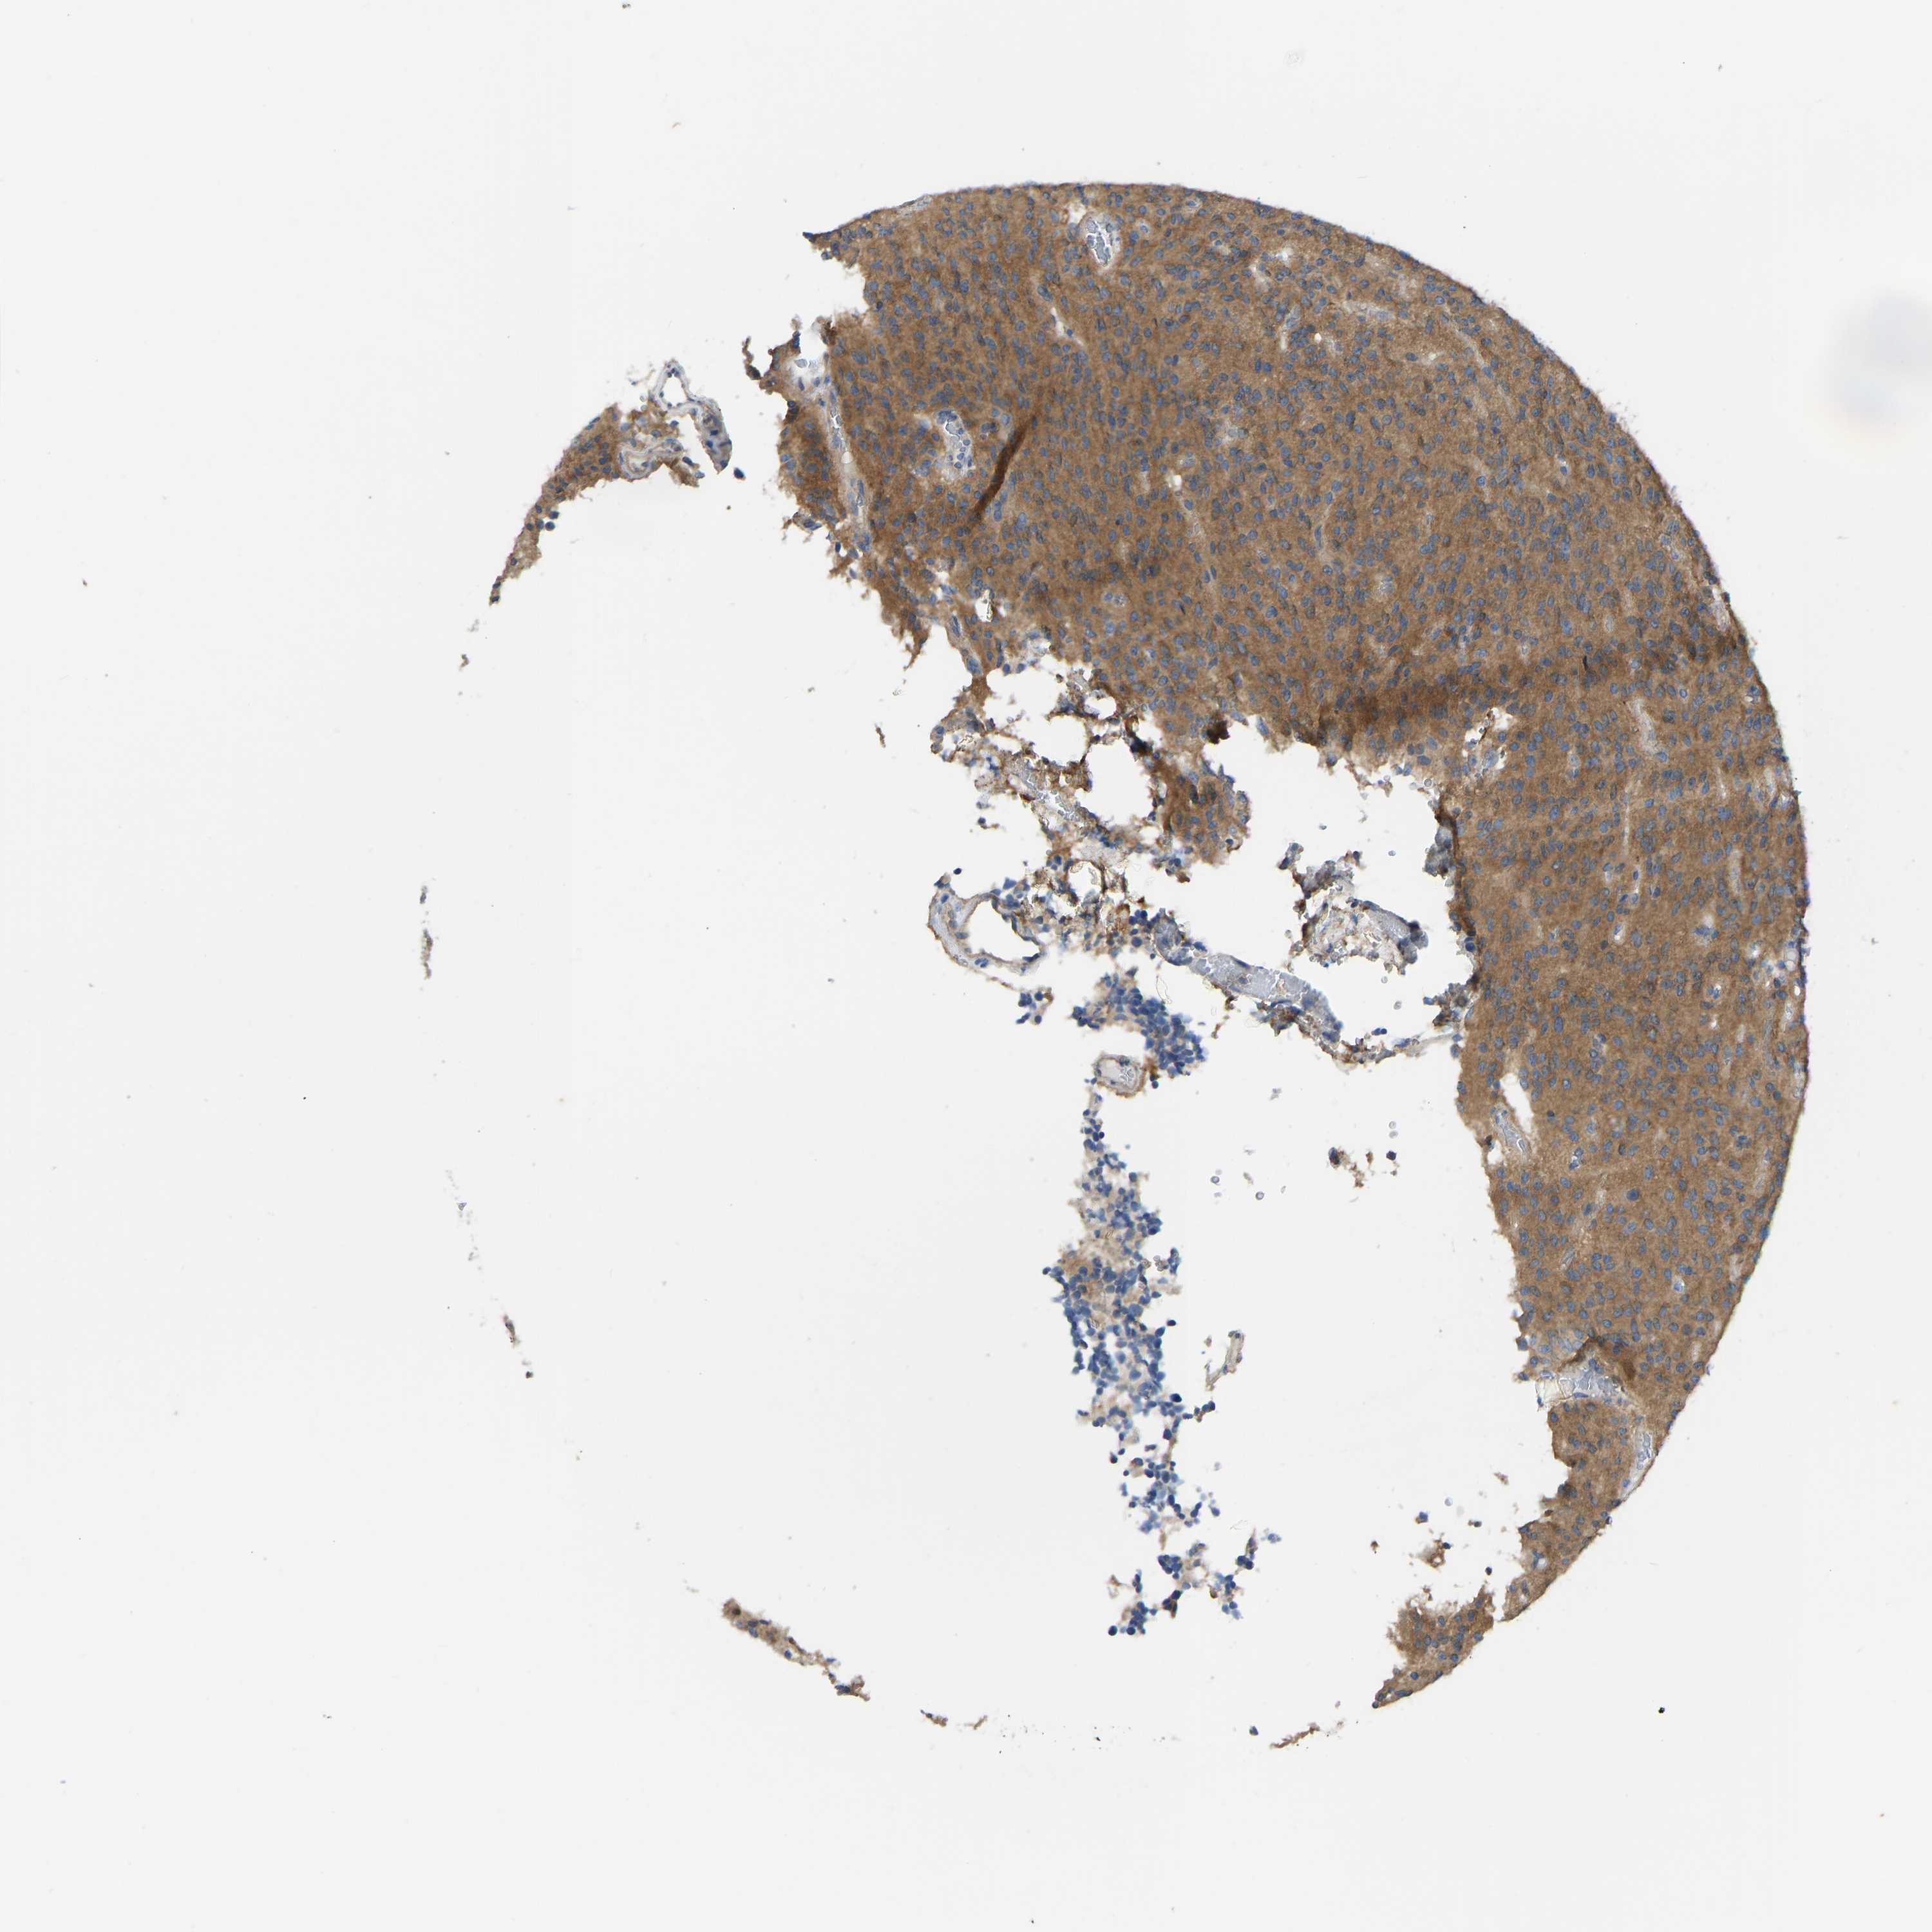

GLIOMA - Protein expressioni

A mouse-over function shows sample information and annotation data. Click on an image to view it in a full screen mode. Samples can be filtered based on level of antibody staining by selecting one or several of the following categories: high, medium, low and not detected. The assay and annotation is described here.

Note that samples used for immunohistochemistry by the Human Protein Atlas do not correspond to samples in the TCGA dataset.

Antibody stainingi

Antibody staining in the annotated cell types in the current human tissue is reported as not detected, low, medium, or high, based on conventional immunohistochemistry profiling in selected tissues. This score is based on the combination of the staining intensity and fraction of stained cells.

Each image is clickable and will lead to virtual microscopy that enables deeper exploration of all samples and also displays staining intensity scores, fraction scores and subcellular localization as well as patient and tissue information for each sample.

Antibody HPA012778

Antibody CAB018581

Staining

High

Medium

Low

Not detected

Intensity

Strong

Moderate

Weak

Negative

Quantity

>75%

75%-25%

<25%

None

Location

Nuclear

Cytoplasmic/membranous

Cytoplasmic/membranous,nuclear

Glioma, malignant, High grade

Glioma, malignant, Low grade